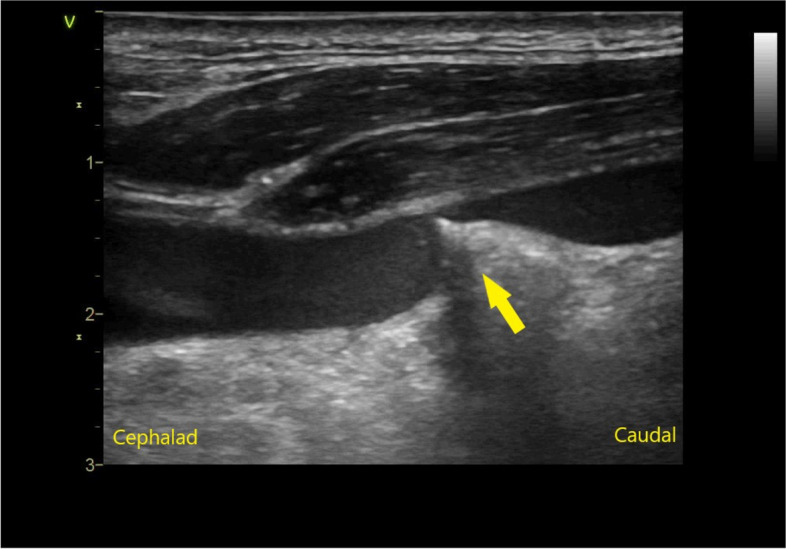

Background: The standard of care for placement of a central venous catheter (CVC) includes a real-time ultrasound (US)-guided technique. We describe a rare case in which the guidewire penetrated the posterior wall of the vessel, forming a knot, which precluded simple removal. This occurred despite the procedure being performed under real-time US guidance. The guidewire was eventually removed under fluoroscopic guidance in a hybrid operation room.

Case presentation: An 89-year-old male underwent the placement of a CVC in the left internal jugular vein. During the US-guided procedure, the guidewire penetrated the posterior wall of the vessel and formed a knot, which impeded simple removal. This was confirmed by radiologic imaging. Using a short sheath and a push-pull technique, the radiologist was able to untangle the knot to allow for catheter removal. The guidewire was safely removed without vascular injury.

Conclusions: A very rare complication of guidewire knotting was observed despite the use of US-guidance during needle and wire placement. The use of US, computed tomography, and fluoroscopy were beneficial for diagnosis, while the hybrid operating room provided the optimal environment for the removal procedure.